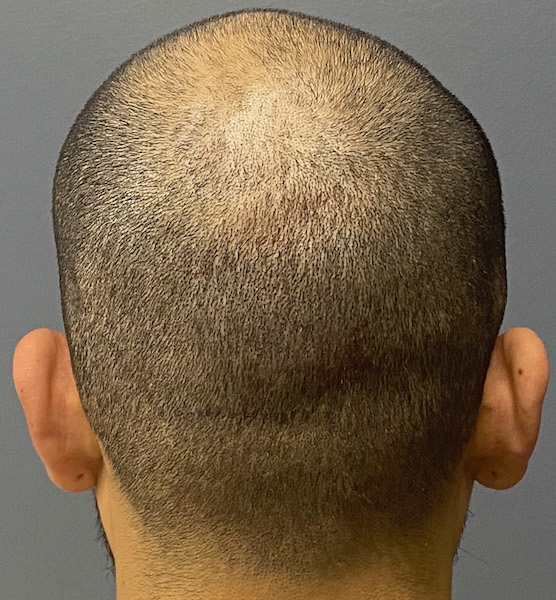

Patient 100

Desire for reshaping of an asymmetric flat back of the head in a shaved head male.

A combined back of the head reshaping procedure was done with a custom skull implant, sagittal ridge reduction and a right temporal muscle reduction.

Desire for reshaping of an asymmetric flat back of the head in a shaved head male.

A combined back of the head reshaping procedure was done with a custom skull implant, sagittal ridge reduction and a right temporal muscle reduction.